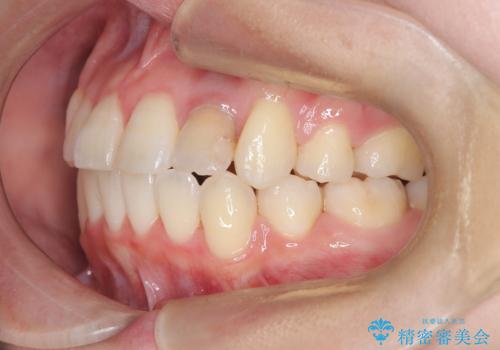

かなり綺麗に並ぶ事ができ大変満足していただけました。

叢生量がかなり多かったのですが、歯肉退縮も失活歯も無くとても綺麗な歯並びになりました。

歯のでこぼこは、歯周病や虫歯のリスクも、とても高いので、見た目のみならず、将来の歯の寿命自体もかなり伸ばす事が出来た治療でした。

歯の寿命を伸ばす為には、歯磨きをし易い環境を作る事がとても大切です。